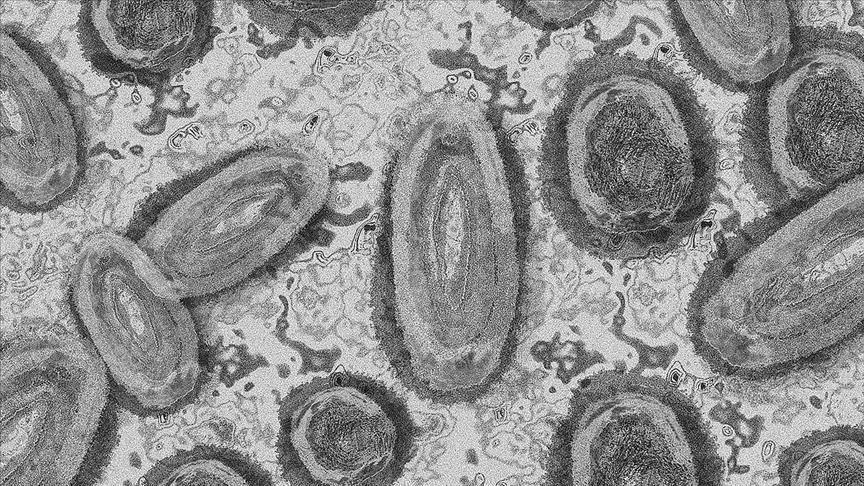

Mpox is an infectious disease caused by the monkeypox virus (MPXV).

The virus, originally known as monkeypox, spreads through direct contact with bodily fluids and causes flu-like symptoms and pus-filled lesions on the skin.